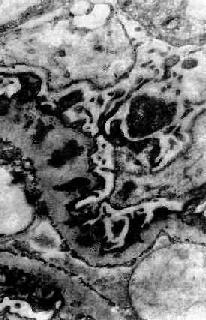

图12-12 新月体性肾小球肾炎

肾球囊壁层上皮细胞增生,其间有单核巨噬细胞浸润形成新月体,肾球囊腔被阻塞